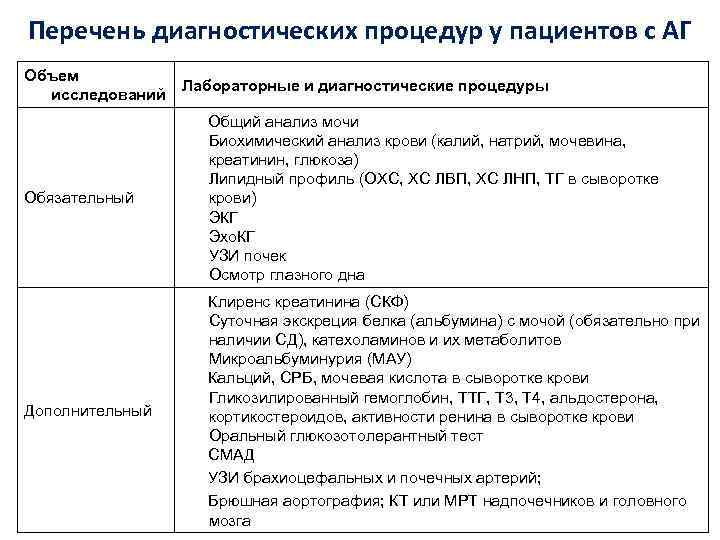

Перечень диагностических процедур у пациентов с АГ Объем Лабораторные и диагностические процедуры исследований Обязательный Общий анализ мочи Биохимический анализ крови (калий, натрий, мочевина, креатинин, глюкоза) Липидный профиль (ОХС, ХС ЛВП, ХС ЛНП, ТГ в сыворотке крови) ЭКГ Эхо. КГ УЗИ почек Осмотр глазного дна Дополнительный Клиренс креатинина (СКФ) Суточная экскреция белка (альбумина) с мочой (обязательно при наличии СД), катехоламинов и их метаболитов Микроальбуминурия (МАУ) Кальций, СРБ, мочевая кислота в сыворотке крови Гликозилированный гемоглобин, ТТГ, T 3, T 4, альдостерона, кортикостероидов, активности ренина в сыворотке крови Оральный глюкозотолерантный тест СМАД УЗИ брахиоцефальных и почечных артерий; Брюшная аортография; КТ или МРТ надпочечников и головного мозга

Перечень диагностических процедур у пациентов с АГ Объем Лабораторные и диагностические процедуры исследований Обязательный Общий анализ мочи Биохимический анализ крови (калий, натрий, мочевина, креатинин, глюкоза) Липидный профиль (ОХС, ХС ЛВП, ХС ЛНП, ТГ в сыворотке крови) ЭКГ Эхо. КГ УЗИ почек Осмотр глазного дна Дополнительный Клиренс креатинина (СКФ) Суточная экскреция белка (альбумина) с мочой (обязательно при наличии СД), катехоламинов и их метаболитов Микроальбуминурия (МАУ) Кальций, СРБ, мочевая кислота в сыворотке крови Гликозилированный гемоглобин, ТТГ, T 3, T 4, альдостерона, кортикостероидов, активности ренина в сыворотке крови Оральный глюкозотолерантный тест СМАД УЗИ брахиоцефальных и почечных артерий; Брюшная аортография; КТ или МРТ надпочечников и головного мозга